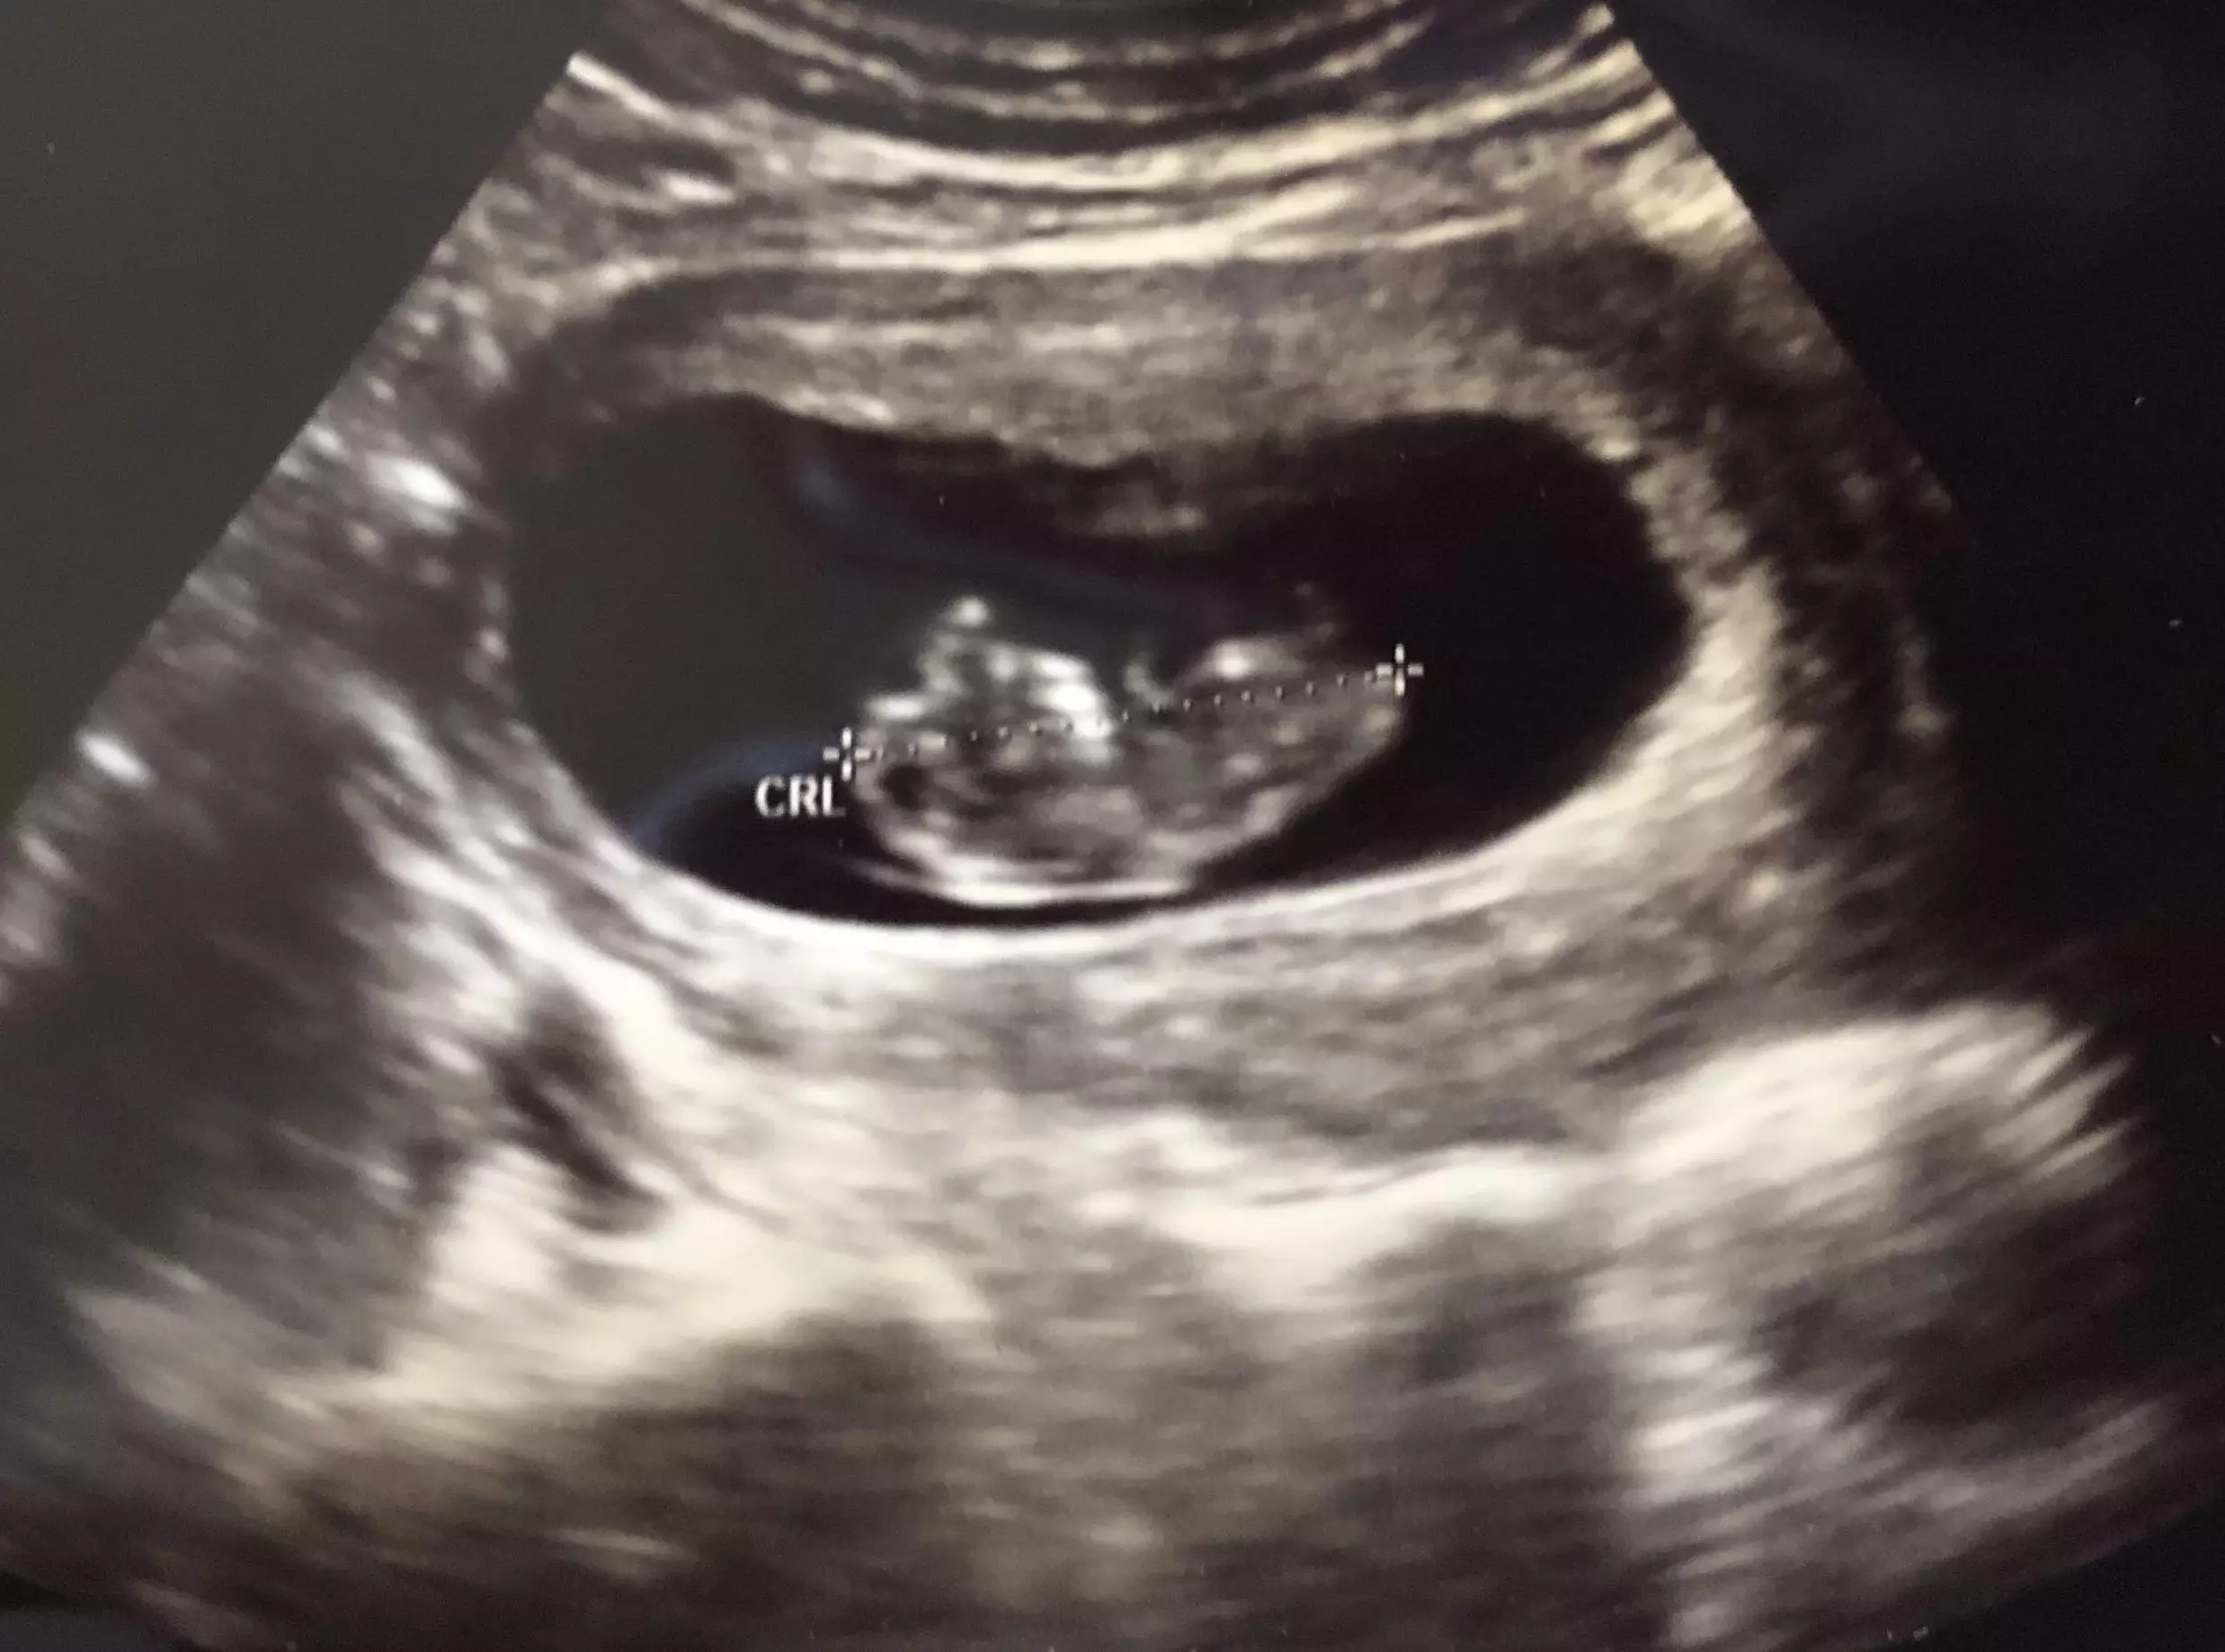

~ I wondered if it was too late…They were wonderful to me. I'm so grateful for everyone taking time out of their day to be by my side. My baby has a strong heartbeat of 168. My next ultrasound is this Wednesday. Putting some strong prayers over my baby and taking it easy.

~ Yes - success. There is a heartbeat. We are praying. Thank YOU so much for your help and taking the call. I'm happy to hear I have options.

~ I am doing well. Had an ultrasound last week and was told it's a baby girl. They said everything looks great and she is very active. I appreciate your help and am so grateful I was able to find your information!!

~ Checkup today at 10w3d and we couldn’t believe how much progress we’ve made over the last month. I can't believe how lucky and blessed I am and every time I look at my baby, I can’t believe there was a time I was unsure. When I heard the heartbeat and saw them moving around in there and how much they’ve grown I was literally brought to tears.